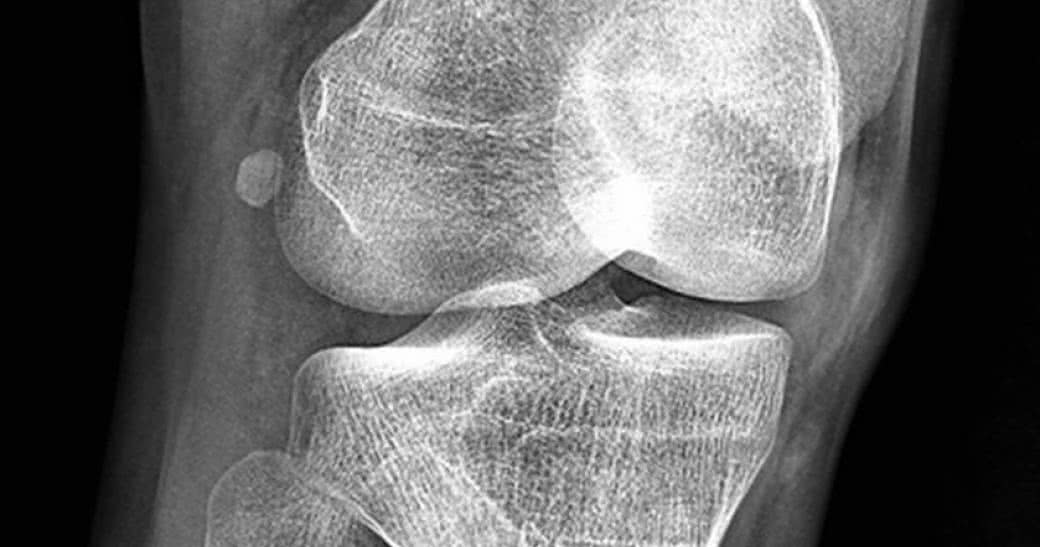

Operacja kolana? Lepiej się zastanów...

Artrodeza kolana jest często jak przysłowiowy strzał w stopę... Badania naukowe dowodzą, że u osób cierpiących na zapalenie stawów w jednym przypadku na trzy nie powinno się jej przeprowadzać!

Amerykańscy naukowcy z Virginia Commonwealth University wskazują, że jedynie 44% operacji to procedury w pełni uzasadnione. Na podstawie analizy, w której wzięto pod uwagę 175 przypadków artroplastyki stawu kolanowego, specjaliści zbadali zasadność przeprowadzonej operacji.

Jeśli wierzyć badaczom z Wirginii, to na 600 tysięcy zabiegów wymiany stawu kolanowego, wykonywanych co roku w Stanach Zjednoczonych, ponad 200 tys. z nich jest zbędnych!

Zasadność przeprowadzenia operacji była podważana w przypadku 22 % badanych, a ponad połowa wszystkich zabiegów wymiany stawu kolanowego została uznana za wątpliwe.

34% procedur zostało uznanych za takie, które nie powinny się w ogóle zdarzyć lub decyzja o ich podjęciu była niewłaściwa.

Zapalenie stawów w tych przypadkach nie powodowało wielkiego bólu kolan, a mobilność pacjentów była zachowana na dobrym poziomie.